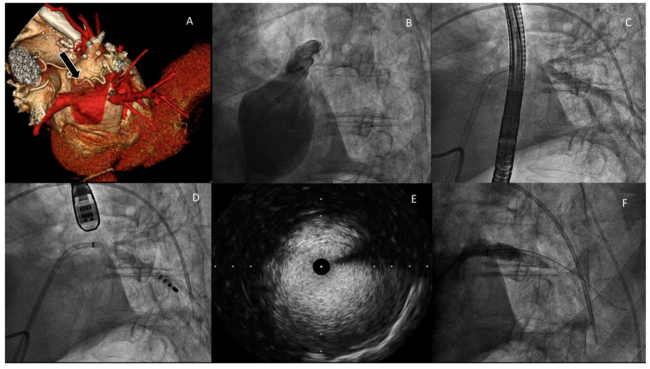

A 69-year-old male with atrial fibrillation radiofrequency ablation 2 years ago was admitted for transcatheter angioplasty of left inferior pulmonary vein (LIPV) stenosis due to recurrent hemoptysis. A cardiac computed tomography (CT) scan was performed showing complete ostial occlusion in the area of the LIPV (Figure 1A). Pigtail angiography through the transseptal sheath was made without visualizing the ostium of LIPV branch (Figure 1B). A brief attempt to cross over with a Mariner and Tacticath catheter (Angiodynamics) was unsuccessful due to difficulty identifying the LIPV ostium. We advanced a Berman catheter (Teleflex) through the contralateral femoral vein and positioned it in a lower branch of the left pulmonary artery. Angiography was performed, visualizing LIPV retrogradely and identifying a short ostial occlusion (Figure 1C). Guided by retrograde injection, the Tacticath was positioned on the LIPV ostium and the occlusion was crossed (Figure 1D). A high-support .035˝ guidewire was advanced into the LIPV and predilated with a 6-mm balloon. The guidewire was exchanged for an angioplasty guidewire and intravascular ultrasound (IVUS) was performed to measure the reference luminal diameter of the vessel distal to the occlusion (Figure 1E). A 9- x 18-mm Restorer stent (iVascular) was implanted. Due to the clear under-expansion, postdilation of the ostium was performed with the stent-balloon at 16 atm with excellent results (Figure 1F and Video 1). The patient was discharged without complications.